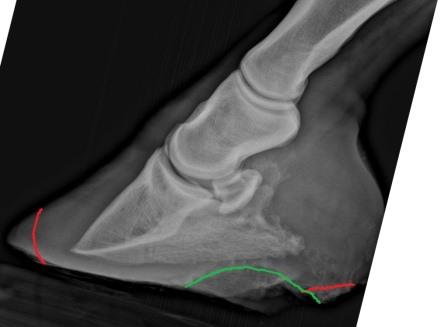

Thank you Dr. Ogelsby, I will print the article and discuss with my farrier and vet. I have attached a trimming game plan one farrier has for this horse. I know you haven't seen the horse, I understand the attempt at trimming to realign but the farrier also mentioned possible casting which I am not familiar with. In the attached pictures the farrier rotated them to show where they think the coffin bone has to be in order for the entire scenario to start healing. The red lines mark

what has to still come off, the green lines mark either thrush or high bars. If the hoof capsule needs it, the farrier will put a cast on, maybe with a sole pad, so that the hoof capsule does not abrade when he is moving around and he will get some stability and comfort. Once the coffin bone inside the hoof capsule is set ground parallel, the wall can grow again where it belongs and the laminar attachment can regenerate.

Do you have any articles on casting or an opinion?left frontright front

Because of the complications of the cast itself (primarily pressure sores), I avoid casting whenever possible even if there is some indication. I don't see the indication for it here so be sure you ask the vet what benefit is expected and be sure it makes sense.